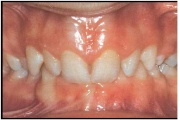

Vali sind huvitav pilt ja me näitame sellega seotud haigust ja sümptomeid